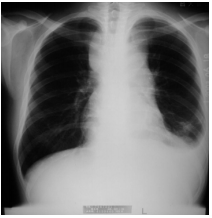

62 一位26 歲男性因發燒、疲倦入院,血液檢查發現血紅素為9.5 g/dL;白血球36,300/µL,其中blast 30.5%, banded neutrophil 4.5%,segmented neutrophil 51%,monocyte 2%,lymphocyte 12%;血小板 103,000/µL。 胸部 X 光如圖所示。下列何者為此位病人最可能的診斷?

(A) lung cancer (B) pneumonia (C) T-lymphoblastic leukemia (D) acute myeloblastic leukemia